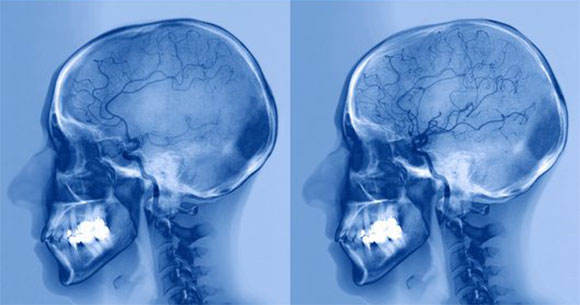

If there is a genuine concern for stroke, it is customary to conduct brain scans to diagnose whether a blocked blood vessel is responsible for the stroke, find out which areas of the brain have been affected, and assess the extent of the damage. The two types of scans commonly used for this purpose are computed tomography (CT) and magnetic resonance imaging (MRI). CT scans are relatively faster and are often used for quick diagnosis of brain bleeding that requires urgent treatment. MRI scans are slower and more accurate than CT scans and are used when the symptoms are complex or when it is unclear where the stroke occurred, as well as after the occurrence of a transient ischemic attack. In both types of scans, doctors can inject a special substance into the patient’s bloodstream to improve the quality of the imaging and allow for a more thorough examination of the blood vessels in the brain.

A before-and-after comparison of brain imaging showing a stroke patient with an artery blockage (left) and the same patient following treatment (right) with drugs that dissolve blood clots to alleviate the blockage. Source: ZEPHYR, Science Photo Library.